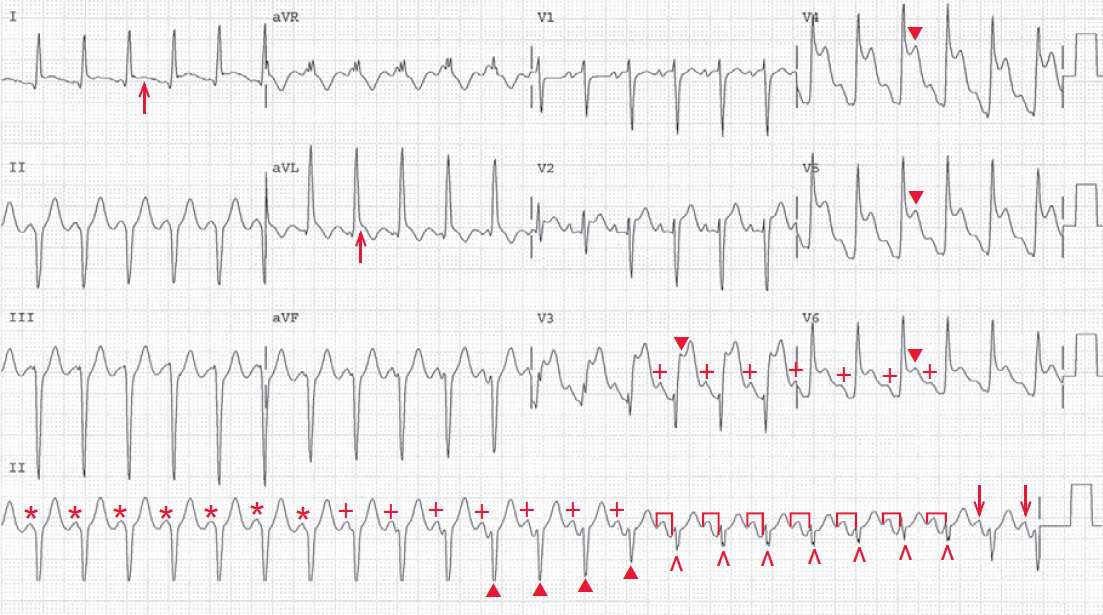

The shows a regular rhythm at a rate of 140 bpm. In the initial portion of the ECG (first 14 QRS complexes), there are regular QRS complexes, each with a duration of 0.12 second.

Although there are no P waves seen in the beginning of the ECG, P waves (+) become obvious by the eighth QRS complex in the rhythm strip. Indeed, there are P waves in the first 7 QRS complexes, which are superimposed at the beginning of the QRS complex (*).

It should be noted that the PR interval gradually increases as the QRS complex duration decreases and changes in morphology. By the fifteenth through the twenty-first QRS complex, there is a stable PR interval (┌┐) (0.16 sec) and a stable QRS morphology (^).

The last two QRS complexes have a P wave before them (↓), but the PR is slightly shorter, the QRS complex morphology is slightly different, and the QRS complex duration is increasing. Hence there is evidence of AV dissociation present with a wide QRS complex.

The changing morphology and duration of the QRS complex that occurs as the PR interval lengths suggests that these are fusion beats (especially complexes 11–14 [▲] where the QRS complex morphology is intermediate between the wide ones and the captured complexes), while the fifteenth through the twenty-first QRS complexes are captured. At the end, there is again fusion (last two QRS complexes). Hence this is a sinus tachycardia with AV dissociation and a ventricular tachycardia.

Since the ventricular rate and atrial rate are identical, this is termed isorhythmic dissociation. It is not clear if this is complete heart block with an escape ventricular rhythm or an accelerated idioventricular rhythm, ie, ventricular tachycardia.

The occurrence of intermittent fusion and capture means that this is an accelerated ventricular rhythm, ie, ventricular tachycardia. When there is a subtle increase in the sinus rate (or a subtle decrease in the ventricular rate), AV capture occurs.

In addition, there is pronounced ST-segment elevation in leads V3–V6 (▼). The ST segments still have a concave morphology. Given the clinical history, the ECG changes are consistent with an acute anterolateral myocardial infarction. Although the complexes in leads I through aVF are ventricular, there is also ST-segment elevation in leads I and aVL (↑), suggesting that there is also involvement of the lateral wall.